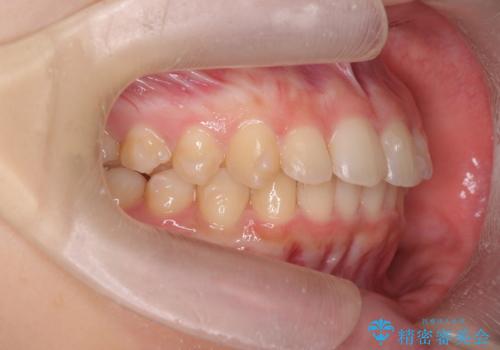

- 突出感のある、前歯の矯正治療を求めて来院されました。

軽度な突出・ガタつきを26枚・約半年の矯正治療期間で計画するインビザラインモデレートプランで治療を始めて行きます。

約半年といった短期間で、前歯の角度やガタつきを改善することができました。